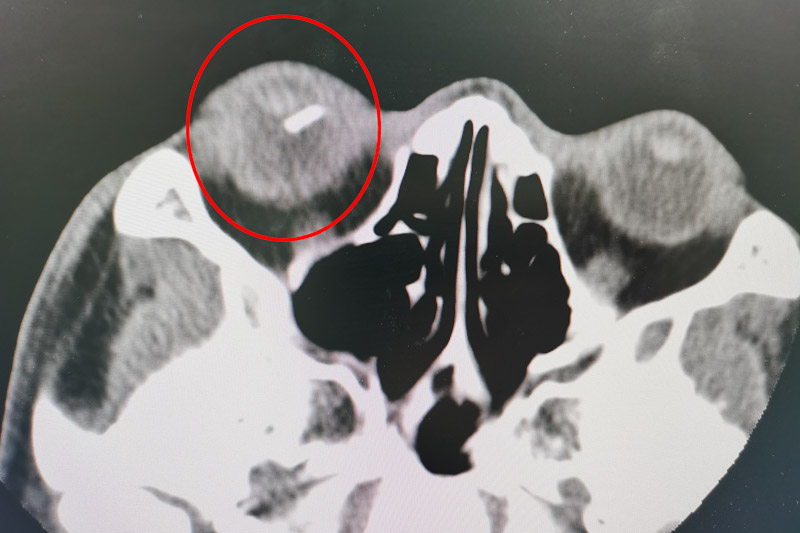

但该眼内手术难度很大,稍有不慎就可能出现眼内出血、眼内感染、玻璃片术中再次掉落损伤视网膜甚至黄斑部的风险。为确保手术万无一失,眼科团队做了详细、周密的术前准备。术中使用微创23G玻璃体切割系统,在眼球上建立直径为毫米级别的套管通道,使用显微器械进行手术处理。通过显微镜可以看到视网膜上亮晶晶的玻璃碎片,玻璃碎片表面光滑,大小是手术切口的十倍左右。施术者小心翼翼从碎片两侧头端、侧面轻轻翻开尝试夹取,稍有不慎,就会损伤视网膜,造成二次伤害。最终凭借高超的技巧,将长1.4cm的玻璃碎片成功取出,保住了患者的眼球。